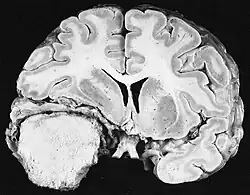

Glioblastoom

De meest voorkomende en kwaadaardige gliaceltumoren zijn glioblastomen. Ze bestaan voornamelijk bij volwassenen uit een heterogene massa van slecht gedifferentieerde astrocytoomcellen. Ze komen meestal voor in de hersenhelften, meer zelden in de hersenstam of het ruggenmerg. Behalve in zeer zeldzame gevallen, zoals alle hersentumoren, reiken ze niet verder dan de structuren van het centrale zenuwstelsel.

Glioblastoom kan ontstaan uit een diffuus (II. graad) of een anaplastisch astrocytoom (III. graad) ontwikkelen. In het laatste geval wordt het secundair genoemd. Wanneer het echter optreedt zonder antecedenten of bewijs van eerdere maligniteit, wordt het primair genoemd. Glioblastomen worden behandeld met chirurgie, bestraling en chemotherapie. Ze zijn moeilijk te genezen en er zijn maar weinig gevallen die langer dan drie jaar overleven.

Aan -MRI toont een intracraniële tumor als een massieve laesie die na gebruik van het contrastmiddel meer luminescent kan worden. Er is echter altijd een signaalafwijking in -Magnetic resonance imaging, die de aanwezigheid van neoplasie of vasogeen oedeem aangeeft. Gewoonlijk is verhoogde luminescentie (contrastversterking) indicatief voor een tumor met een hogere graad van maligniteit. Kenmerkend voor glioblastoom is een contrastring, waarbij het lichtgevende deel overeenkomt met het vitale deel van de kwaadaardige tumor en het donkerdere -hypointens gebied dat overeenkomt met weefselnecrose.